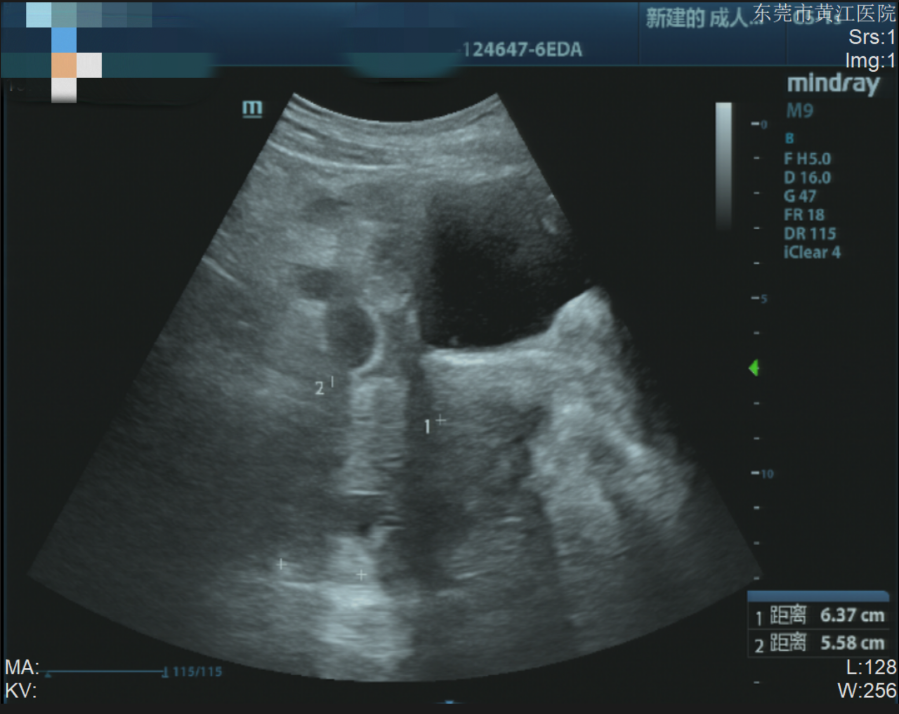

完善血常规及腹部彩超后,刘女士被诊断为“妊娠合并急性阑尾炎”,随后被收入普外科。普外科医生评估后建议尽快手术治疗。